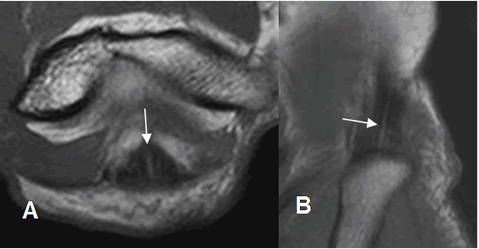

En la ecografía los tendones se identifican como estructuras hipoecoicas, con un patrón fibrilar y en relación con los sitios de origen o inserción. (Fig 15 y 16).

Fig 15. Tendones normales en ecografía.

A: Vista longitudinal, sobre la inserción del tendón del bíceps.

B: Inserción del tríceps, en vista longitudinal.

Fig 16. Tendones normales en ecografía.

A: Vista longitudinal, en el origen de los flexores.

B: Origen de los extensores, en vista longitudinal.